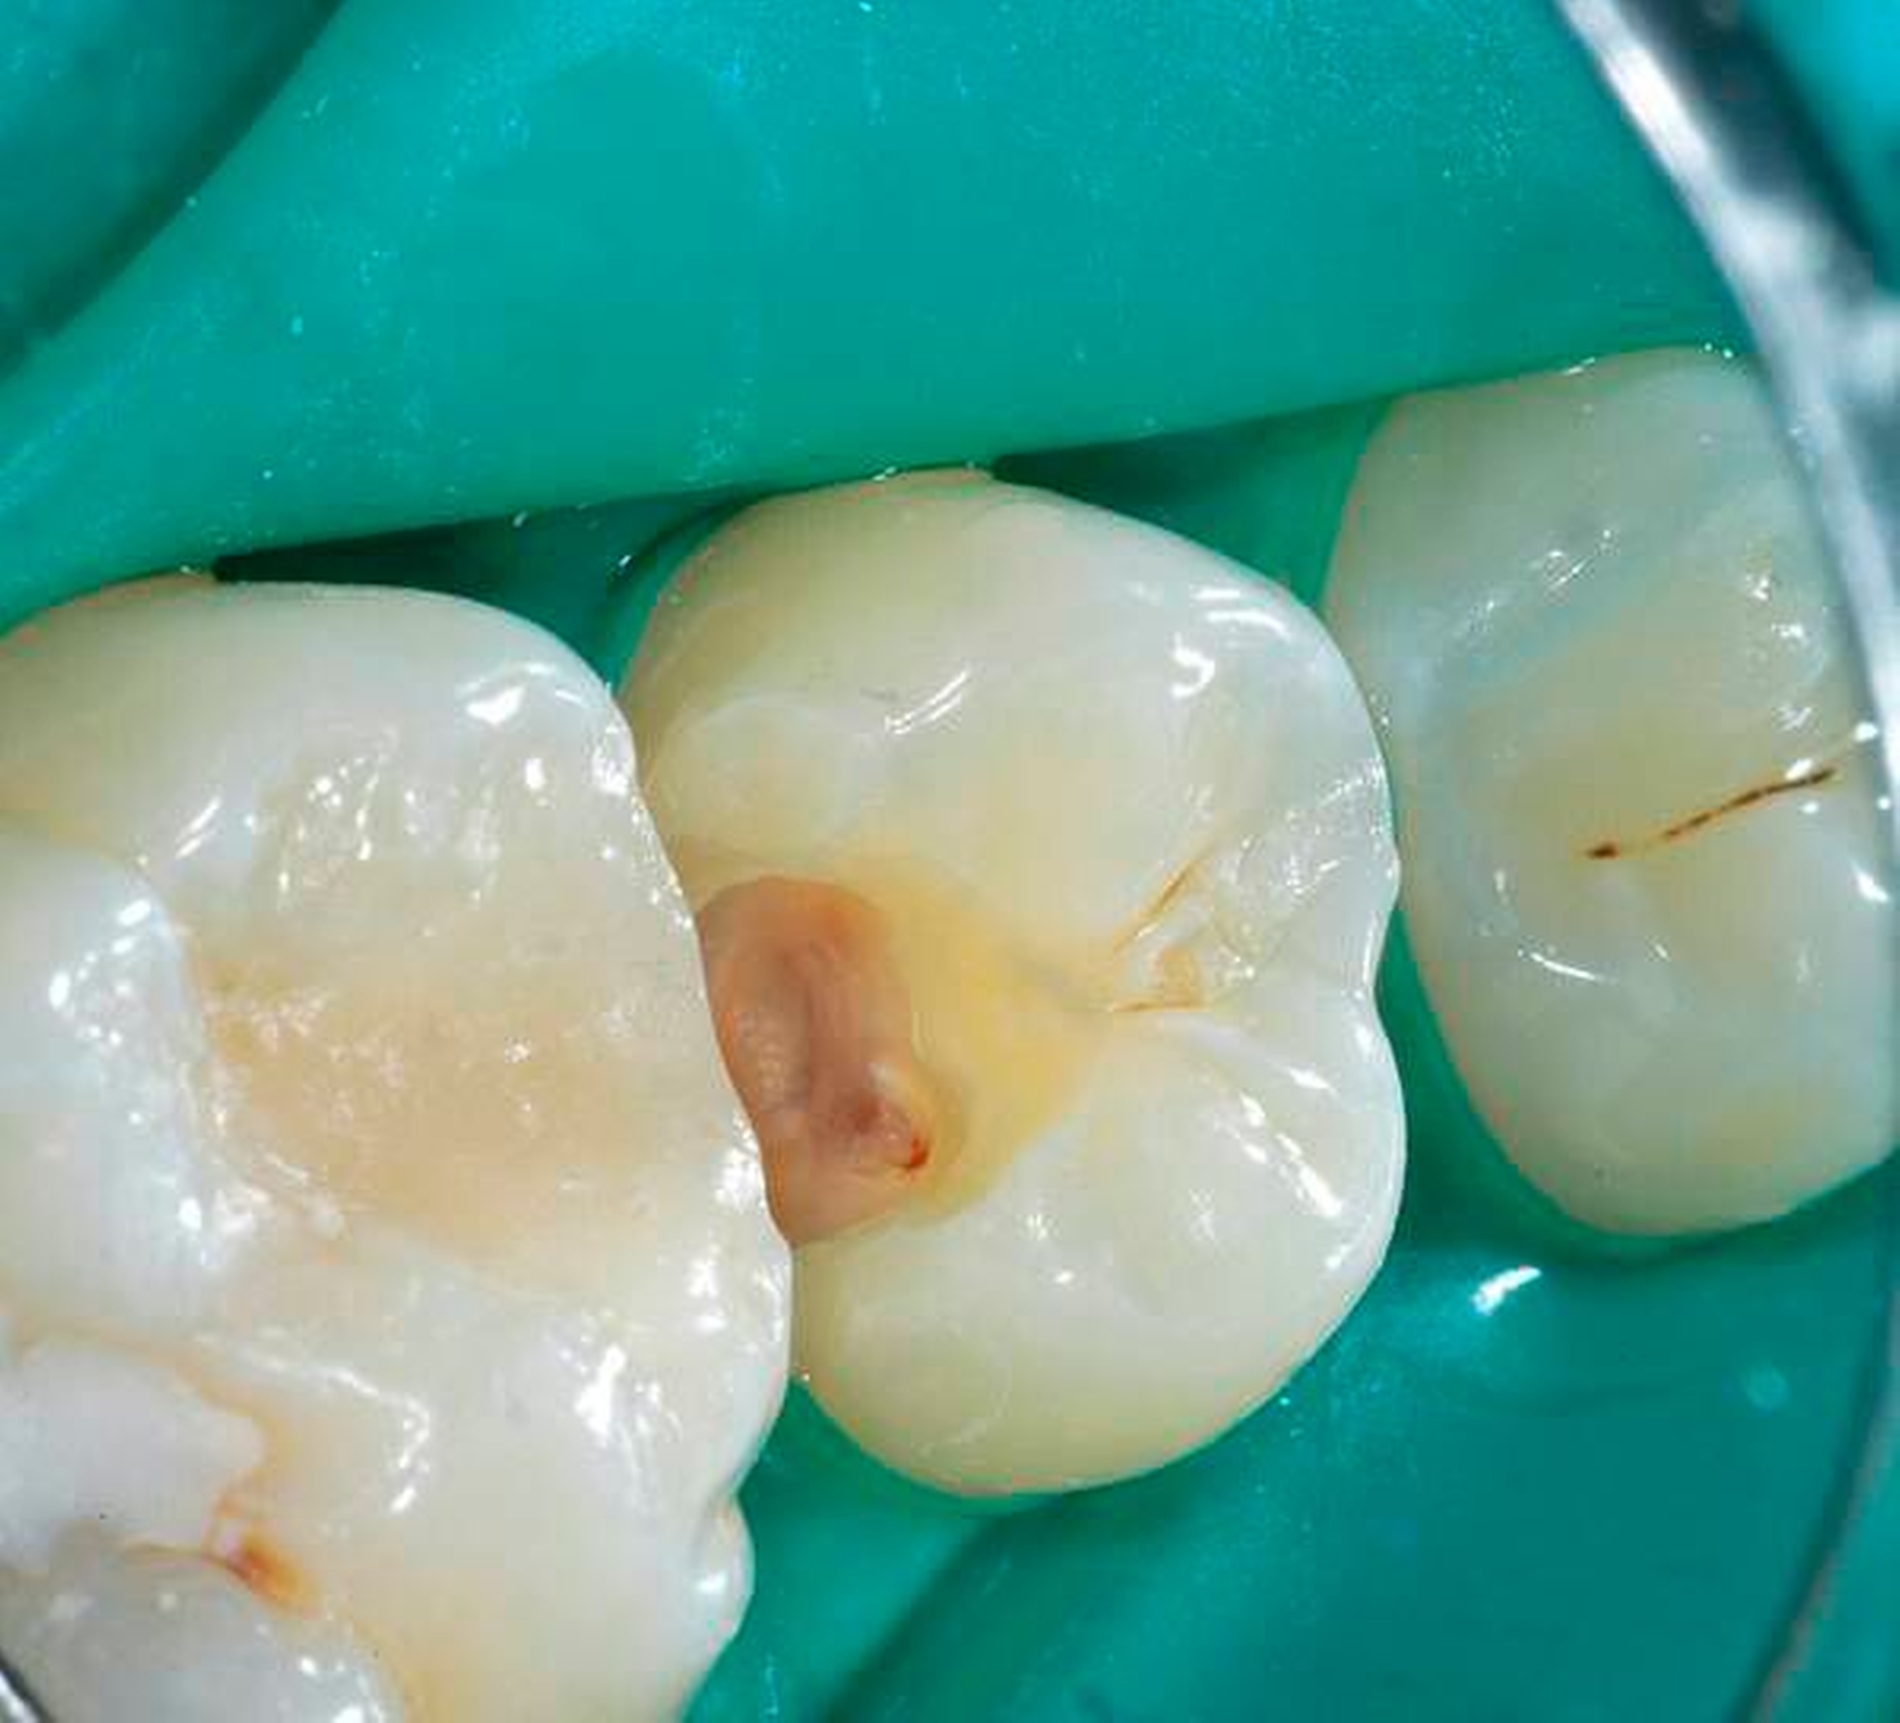

Nachgewiesenermaßen können Calciumsilikat-Zemente die Pulpa zur Bildung von Hartgewebe (Tertiärdentin) stimulieren und sind daher für die Versorgung tiefer kariöser Defekte nach Exkavation und somit für die Vitalerhaltung der Pulpa sehr gut geeignet [15, 21]. Nach indirekter Überkappung mit Biodentine kommt es reproduzierbar zur Ausheilung einer reversiblen Pulpitis [45]. Auch wenn mehr klinische Langzeitstudien zur Vitalerhaltung der Pulpa mit Calciumsilikat-Zementen wünschenswert sind, scheinen nach bisheriger Datenlage Calciumsilikat-Zemente für die indirekte Überkappung der Pulpa besser geeignet zu sein als Calciumhydroxid [2]. Für die direkte Überkappung wurde nachgewiesen, dass Calciumsilikat-Zemente zu besseren klinischen Ergebnissen und höheren Erfolgsraten führt als Calciumhydroxid [50, 60, 63]. Hinsichtlich der Hartgewebebildung ist es dabei unerheblich, ob man ein MTA-Zement oder Biodentine verwendet. Beide Arten von Calciumsilikat-Zement führen beim Menschen zu einer identischen Hartgewebsbrückenbildung [68] (Abbildungen 3 bis 10).